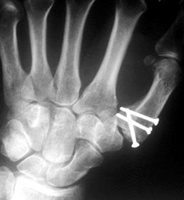

Geschlossene Reposition und Stabilisierung

mit dem Minifixateur

| Zunächst wird versucht die Fraktur

geschlossen zu reponieren. Gelingt dies, steht die Indikation für

die Anwendung des Minifixateur fest. Zwei Schrauben werden in den

Handwurzelknochen und zwei weitere Schrauben den 1. Mittelhandknochen

eingebracht. Durch den Zug am Daumen läßt sich die Bennetfraktur

stufenfrei reponieren. Danach wird der montierte Minifixateur fixiert.

Die Entfernung des Minifixateur ist nach 4 Wochen möglich. |